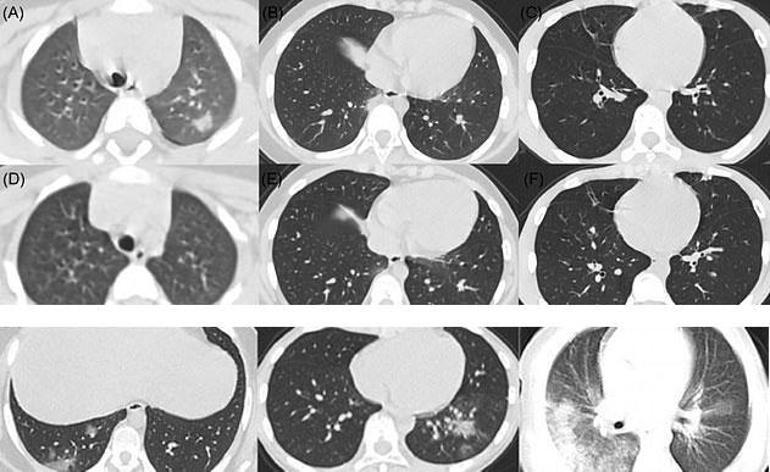

Https Www Turkrad Org Tr Assets Pdfdocs Covid 19 Radyolojik Bulgular 30 3 2020 Pdf

Https Turkradyolojiseminerleri Org Content Files Sayilar 7 Buyuk 304 315 Pdf